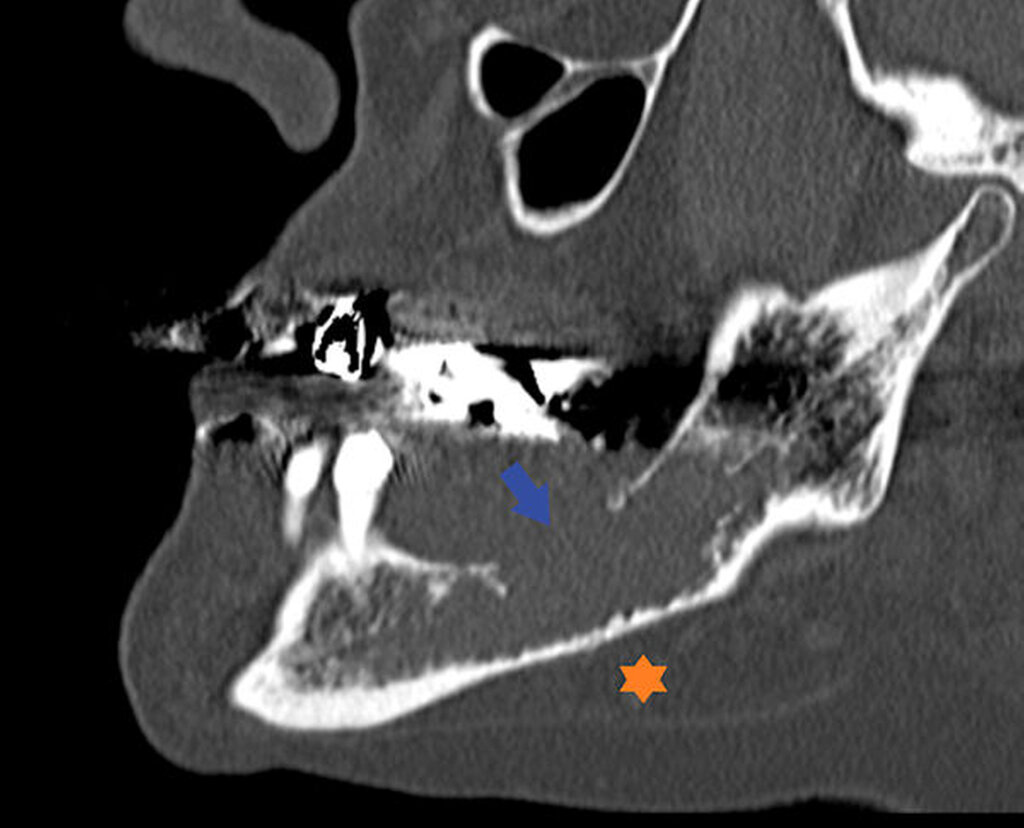

Der extraorale Untersuchungsbefund ist unauffällig. Enoral ist eine fluktuierende Schwellung im Bereich des zahnlosen Alveolarkamms des linken Unterkiefers tastbar. Im angefertigten Orthopantomogramm (OPTG) ist eine zystische Raumforderung im Bereich des Unterkiefers zu erkennen (Abbildung 1). In der anschließenden dreidimensionalen Bildgebung (CT) stellt sich eine glatt berandete, zystische Raumforderung im Bereich des linken Kieferwinkels dar (Abbildung 2).